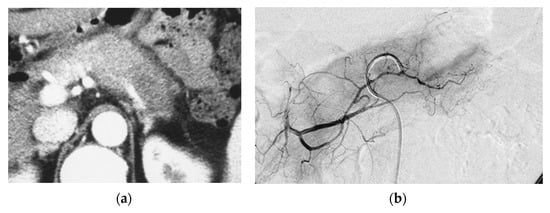

Figure 1.

Pilot study. A 66-year-old female had locally advanced pancreatic carcinoma at body and tail. An arterial administration of DNA crosslinking agents achieved good tumor necrosis. Patient had died after 12 months. Dense retention (dense contrast materials in area >50% of tumor). (a) Postcontrast CT shows a mass at the pancreatic tail. A hypodense mass occupies pancreas body and tail encasing splenic vein (arrow). (b) Superselective dorsal pancreatic angiography shows severe encasement of the transverse pancreatic artery. Arrows indicate the presence of a hypovascular mass. (c) CT immediately taken after administration of the drugs mixed with contrast media shows dense contrast retention in area >50% of tumor. (d) Follow-up CT two weeks after the superselective infusion shows massive necrosis in the tumor.